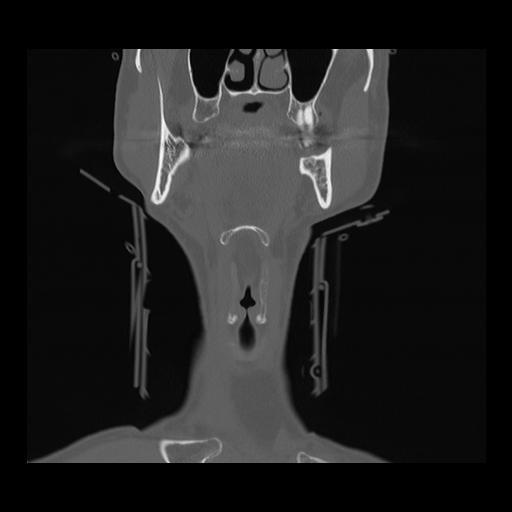

16 HUESO,,Coronal,2.000,HUESO,Coronal,